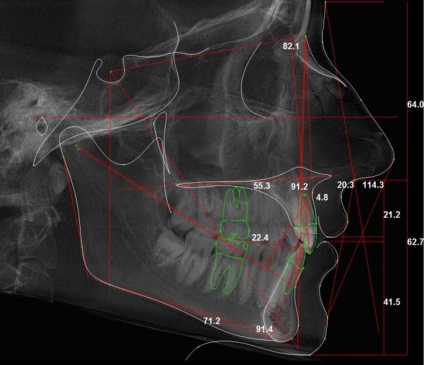

Miután az összes, a leghatékonyabb kezelési tervet képezhet csak azonosításával összes funkcióját a probléma nagysága: az arány a méret a csontok és a lágy szövetek, a pontos helyét a fogak, a szögek a dőlés és a mértéke elmozdulás. TWG is egy képet a fej és a folyamat korrekció, vagy annak befejezését követően (a változások nyomon követése).

A rendszer segítségével a munkacsoport tehető világossá panoráma képet a koponya profilja és teljes arcát. 3 elválasztott alkotnak diagnózist.

- Munkacsoport oldalnézetben szükséges betegek malocclusion. Oldalsó lövés, akkor a legpontosabban azonosítani patológia felépítése a fogászati rendszert, és hozzon létre egy optimális tervet Javítás. A kutatás ezen vetülete, hogy meghatározza a szög az alsó elülső fogak, különösen azok helyét, valamint figyelemmel kíséri a kezelést, és kiszámítja annak időtartamát. Mindenki, aki azt tervezi, hogy javítsa a nadrágtartó, mindig biztos lehet abban, hogy ezt a képet.

Dekódolására egy speciális számítógépes program: